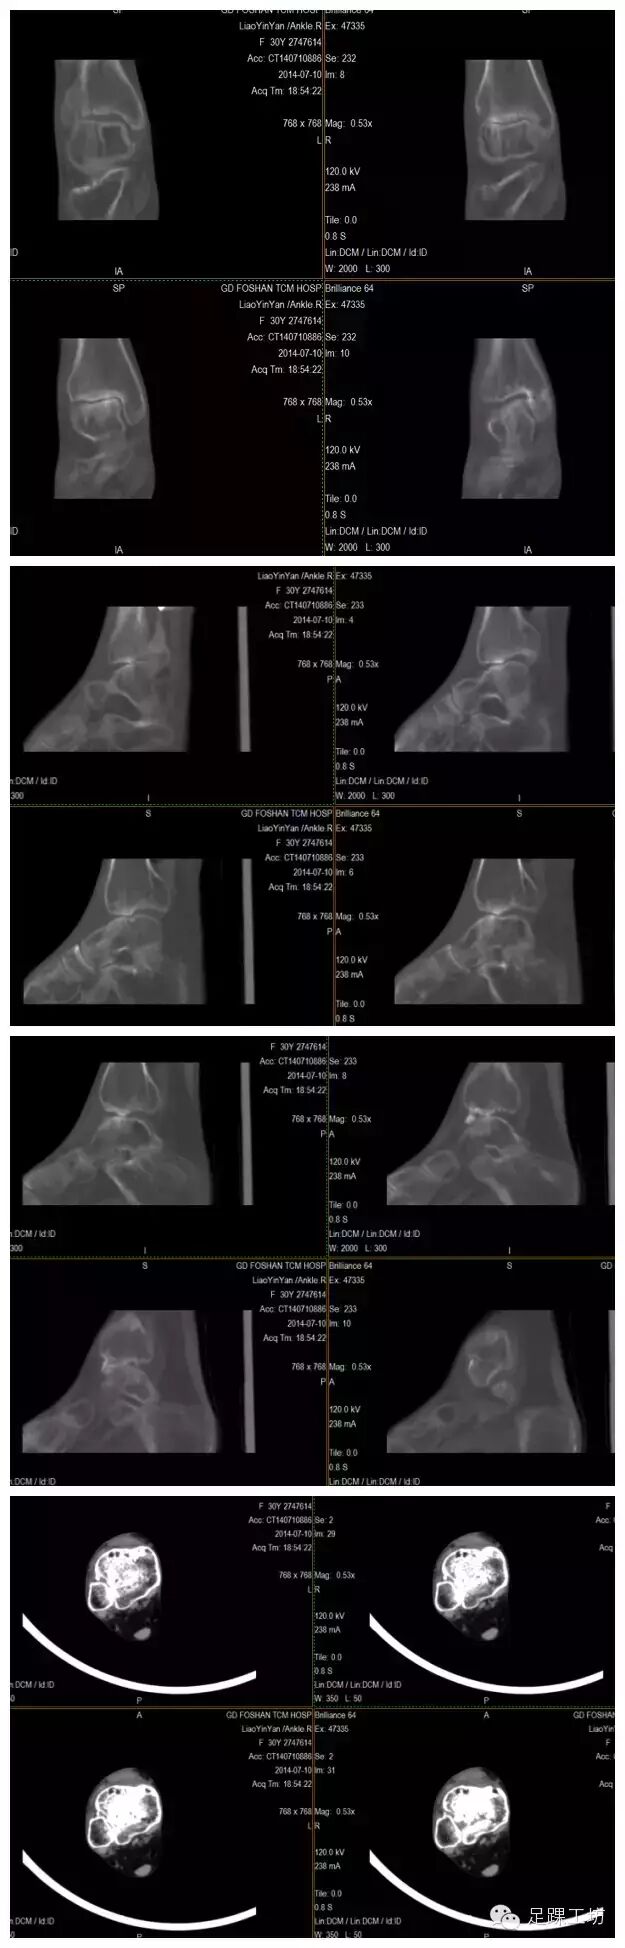

CT重建

CT